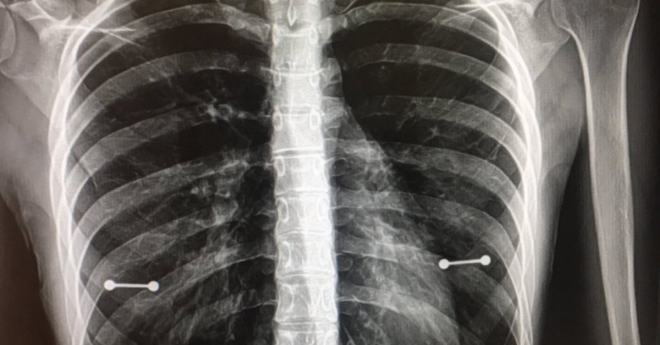

• Pierced Nipples X-Ray

Mom Finds Out About Daughter’s Pierced Nipples Thanks to X-Ray